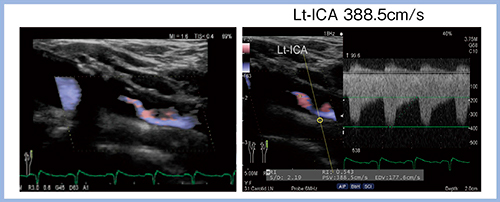

リニアST-CWドプラモード(Linear CW)では,リニアプローブでの連続波(CW)ドプラ走査が可能であり,セクタプローブに持ち替えることなく高速血流を評価することができる。実際の高度狭窄の症例では,388.5cm/sの超高速な血流を評価可能であった(図1)。

図1 リニアST-CWドプラモードによる高速血流の評価